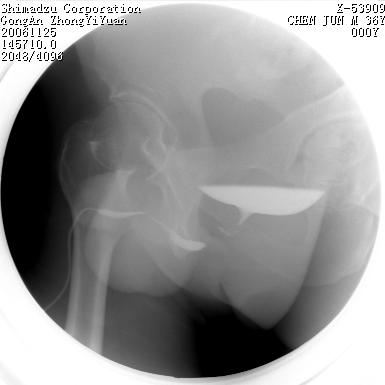

男 66岁 排尿困难半年;此人腹腔及腹膜后积液.

尿道充盈缺损,考虑占位.

后尿道内充盈缺损;前列腺结石。

dyqct 老师,你好,谢谢你的精彩点评及标示,看的出来你是一位务实严谨的专家;但我有一点不明白的是:假如

是结石或息肉,为什么在不同的时候形态会有变化?另有一点须说明的是尿道两边的高密度阴影应该是造影剂逆流吧.

1、后尿道的充盈缺损有变化可能与压力有关;

2、两侧后尿道周围的略高密度影亦有可能为造影剂逆流,有条件的话做个ct吧!

后尿道狭窄,其中可见充盈缺损,我认为应先排除结核.

后尿路精阜水平充盈缺损,考虑结石或占位病变可能,建议mri检查,精阜水平尿路周围条索状密度增高影,考虑造影剂逆流入输精管或周围静脉。